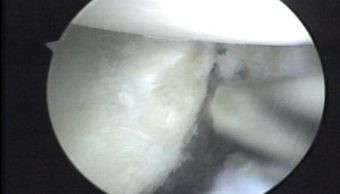

Se observa la desinserción del complejo cápsulo ligamentario anterior, lesión de Bankart